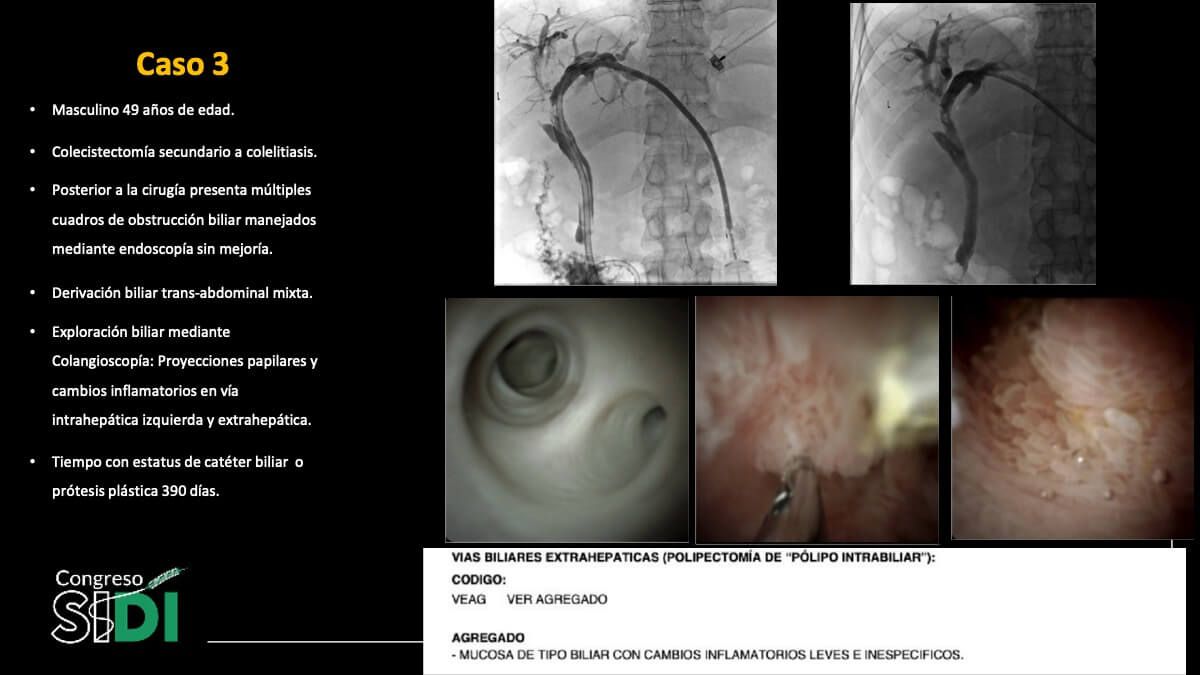

Cambios tisulares en el epitelio biliar inducidos por prótesis plásticas: Evidencia colangioscópica e histológica

Dr. Carlos Saldívar